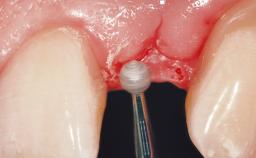

The video demonstrates implant placement using a surgical stent according to the principle of prosthodontically driven implant placement. The deficient ridge is augmented with locally harvested autologous bone chips, a superficial layer of xenogenic DBBM particles and a resorbable collagen membrane. The surgery is completed with a precise, tension-free primary wound closure.

Bone Volume Deficient horizontally, allowing simultaneous augumentation